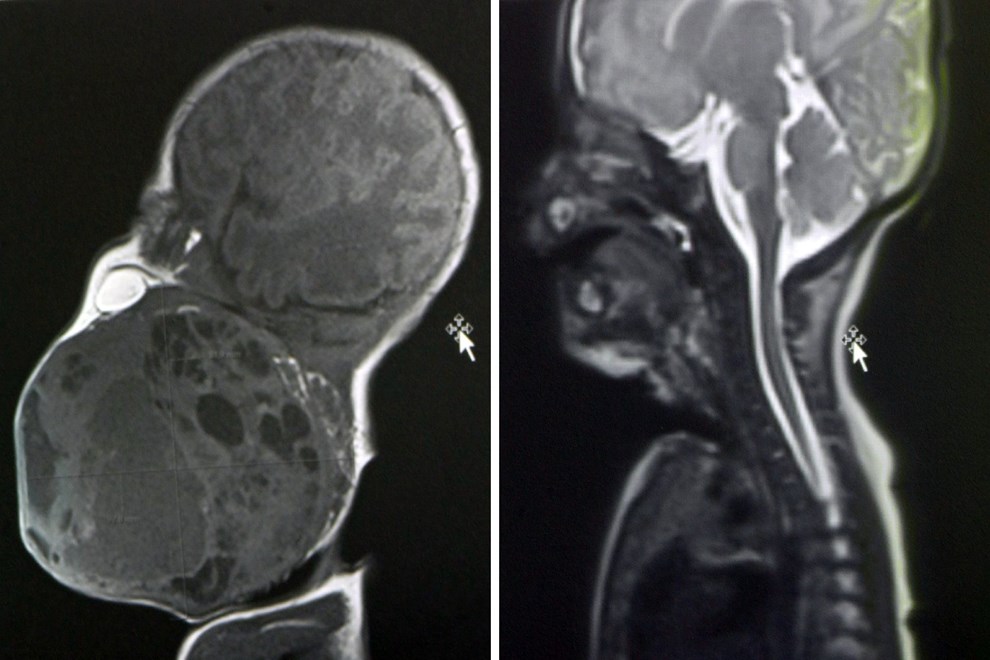

Prema nalazima magnetske rezonance prije poroda, tumor je bio gotovo veličine djetetove glave i zatvarao je dišne putove. Dijete bi bilo životno ugroženo ako bi se rodilo normalnim putem, stoga je tim liječnika morao razraditi i biti spreman na nekoliko varijanti liječenja, a na kraju je profunkcionirala prva opcija.

"Tijekom carskog reza, kada je otvorena maternica, djetetova glava je izvađena, a ostatak tijela je bio u maternici pa je dijete bilo vezano za placentu i putem pupkovine dobivalo kisik. Pristupili smo glavi i pokušavali uspostaviti dišni put", objasnila je pročelnica Zavoda za neonatologiju i intenzivnu medicinu Ruža Grizelj. U sali je, kaže, bilo 20 ljudi.

Dijete je izvađeno kompletno izvan maternice, podvezana je pupkovina i nakon što smo ga stabilizirali, istoga dana je učinjeno kompletno odstranjenje tumora s obzirom na to da smo nekoliko sati nakon samog poroda primijetili u intenzivnoj da se tumor povećava", rekla je Grizelj.

Voditelj Odjela za fonijatriju Ratko Prstačić pojasnio je da je patohistološka dijagnoza pokazala da se radi o teratomu, generalno dobroćudnom tumoru, ali s potencijalnom malignom opasnošću pa će dijete trebati onkološko praćenje, no druga terapija trenutačno nije potrebna.